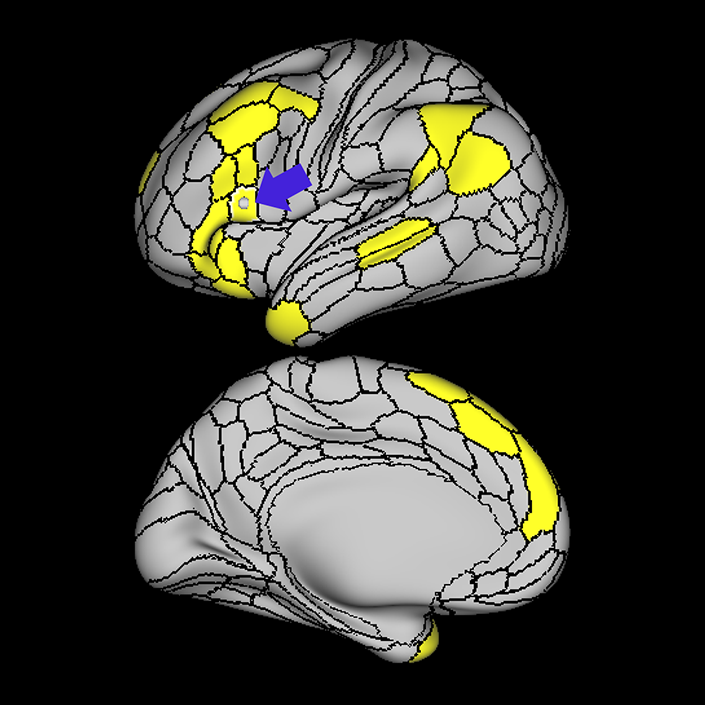

ᐅ SummaryArea 44: part of the inferior frontal gyrus of the lateral frontal lobe. Translates abstract and intentional information in the prefrontal cortex to more detailed representations to help guide the production of verbal and manual actions. In addition to its known association with Broca's area, is sometimes represented as part of Broca's complex ᐅ Where is it?Area 44 is at the posterior most part of the inferior frontal gyrus. It is the anterior bank of pars opercularis of the IFG. ᐅ What are its borders?Area 44 borders area 45 anteriorly and area 6r posteriorly. Area 8C is its medial border and its inferior border is wedged between then upper borders of Areas 6R and 6V. Its superior edge borders IFSp and IFJa. Its opercular surface is FOP4. ᐅ What are its functional connections?Area 44 demonstrates functional connectivity to areas SFL, IFSp, IFJa, 45, 47s, 47L, 9a, 9m, 8AV, 8BL and 8C in the dorsolateral frontal lobe, area 8BM in the medial frontal lobe, area 55b in the premotor areas, areas FOP5, AVI and PSL in the insula- opercular region, areas TGd, STSdp and STSvp in the temporal lobe, areas PFm, and PGi in the inferior parietal lobe, and no areas in the medial parietal lobe. ᐅ What are its white matter connections?Area 44 is structurally connected to the arcuate/SLF and the FAT. Connections with the arcuate/SLF project posteriorly and wrap around the Sylvian fissure to the middle temporal gyrus to end at TE1a and TE1m. There are also projections from the arcuate/SLF before it terminates to parcellations A5 and STSdp. The majority of the inferior connections of the frontal aslant tract end at 44, the tract is connected superiorly to superior frontal gyrus parcellations SFL, 6ma and s6-8. Local short association bundles are connected with 45 and 8C. White matter tracts from 44 in the right hemisphere have less consistent connections with the arcuate/SLF. ᐅ What is known about its function?Area 44 translates abstract and intentional information in the prefrontal cortex to more detailed representations to help guide the production of verbal and manual actions. Area 44, in addition to its known association with Broca's area, is sometimes represented as part of "Broca's complex", including Brodmann Areas 45, 46, 47 and the mesial supplementary motor area of 6, which contribute to a frontal-subcortical circuit. The right pars opercularis has also been implicated in cognitive inhibition in the overall context of working memory. |

A: lateral-medial

B: anterior-posterior

C: superior-inferior

DTI image |